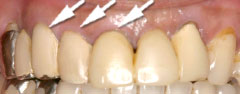

| 歯茎にプラーク(歯垢着が)と歯石の沈認められます。歯肉が腫れ、出血がありました。 | 歯科衛生士の治療と、ブラッシング技術の向上により、歯茎が引き締まり健康的な状態になりました。 | |

| 切除療法の目的は、しっかりと虫歯を取り除き、健全な歯質の獲得と生理的骨形態を付与することす。治療後の歯肉も、高い清掃性、長期安定性を兼ね揃え、永続性が期待できます。(一方で、歯の形態が長くなる・治癒に時間がかかりますので、切除療法と組織付着療法の術式選択は、患者様とのお話合いの上で決めて行きます。) | |||